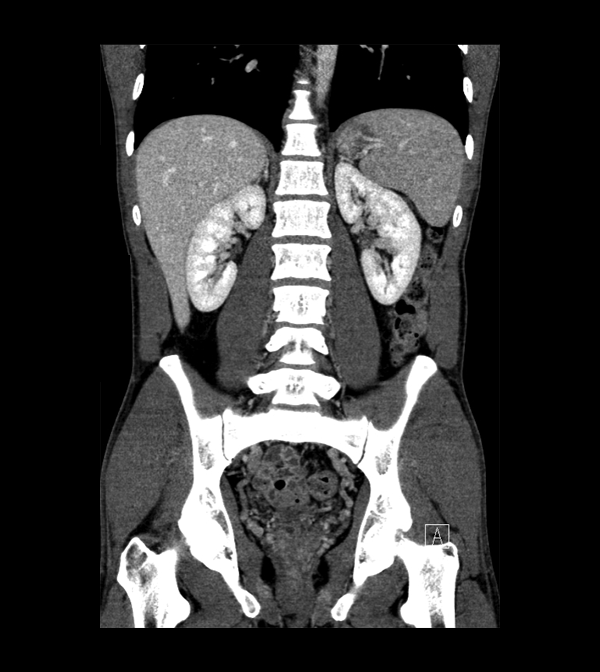

Body

Covers abdominal CT anatomy.